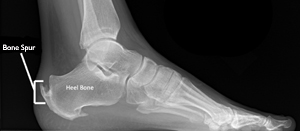

After consulting with two surgeons, they determined I had two bone spurs in my right heel. One is a Haglund’s Deformity and the other on the bottom, is a calcaneal spur (heel spur). The bursa on the back of the heel from the Haglund’s deformity was no longer fluid filled and had formed a large, painful ball which was irritating the tendon. There were two options for surgery. One would have me off my feet for eight weeks with a possible eight month or longer recovery. The second option was less invasive but still required three complete weeks of no weight-bearing then several weeks in a boot, but it would not totally fix the problem. The thing that scared me most was being told that if I fell, I could damage the foot more than it was before surgery from either procedure. The second option recommended orthotics after surgery, but the surgery had to be done first.

Below is an x-ray I found online that illustrates what my bone spurs look like. The tenonitis in the back of the heel has progressed to tendonosis.